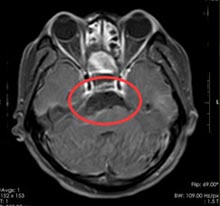

在广东三九脑科医院综合神经外科,经鼻蝶鞍神经内镜下行颅咽管瘤切除术,术程顺利,肿瘤全部切除。

术后患周女士视力没有任何影响,术后第二天便可坐起,并正常饮食,内分泌功能没有影响。